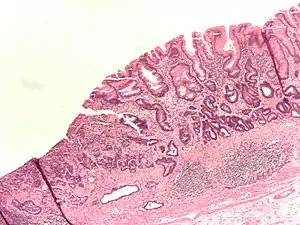

- Gastric adenocarcinoma is a malignant epithelial tumour, originating from glandular epithelium of the gastric mucosa. Stomach cancers are about 90% adenocarcinomas.[57] Histologically, there are two major types of gastric adenocarcinoma (Lauren classification): intestinal type or diffuse type. Adenocarcinomas tend to aggressively invade the gastric wall, infiltrating the muscularis mucosae, the submucosa and then the muscularis propria. Intestinal type adenocarcinoma tumour cells describe irregular tubular structures, harbouring pluristratification, multiple lumens, reduced stroma ("back to back" aspect). Often, it associates intestinal metaplasia in neighbouring mucosa. Depending on glandular architecture, cellular pleomorphism and mucosecretion, adenocarcinoma may present 3 degrees of differentiation: well, moderate and poorly differentiated. Diffuse type adenocarcinoma (mucinous, colloid, linitis plastica or leather-bottle stomach) tumour cells are discohesive and secrete mucus, which is delivered in the interstitium, producing large pools of mucus/colloid (optically "empty" spaces). It is poorly differentiated. In signet ring cell carcinomas, the mucus remains inside the tumour cell and pushes the nucleus to the periphery, giving rise to "signet-ring cells".

Adenocarcinoma of the stomach and intestinal metaplasia. H&E stain.